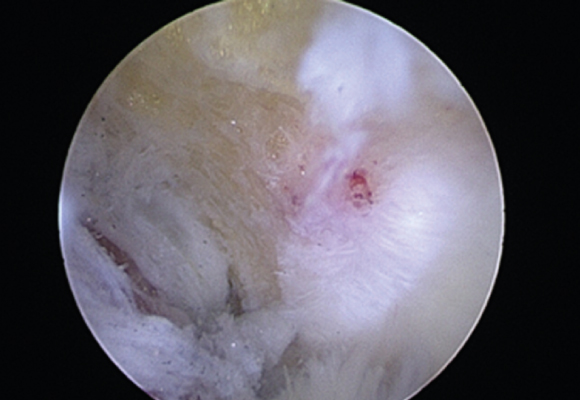

손상된 회전근개를 다듬어 주고 봉합해 주는 수술 시행

ㆍ환자의 동의를 받은 자료이며, 이미지 사진은 실물과 다를 수 있습니다. (16.09.30)